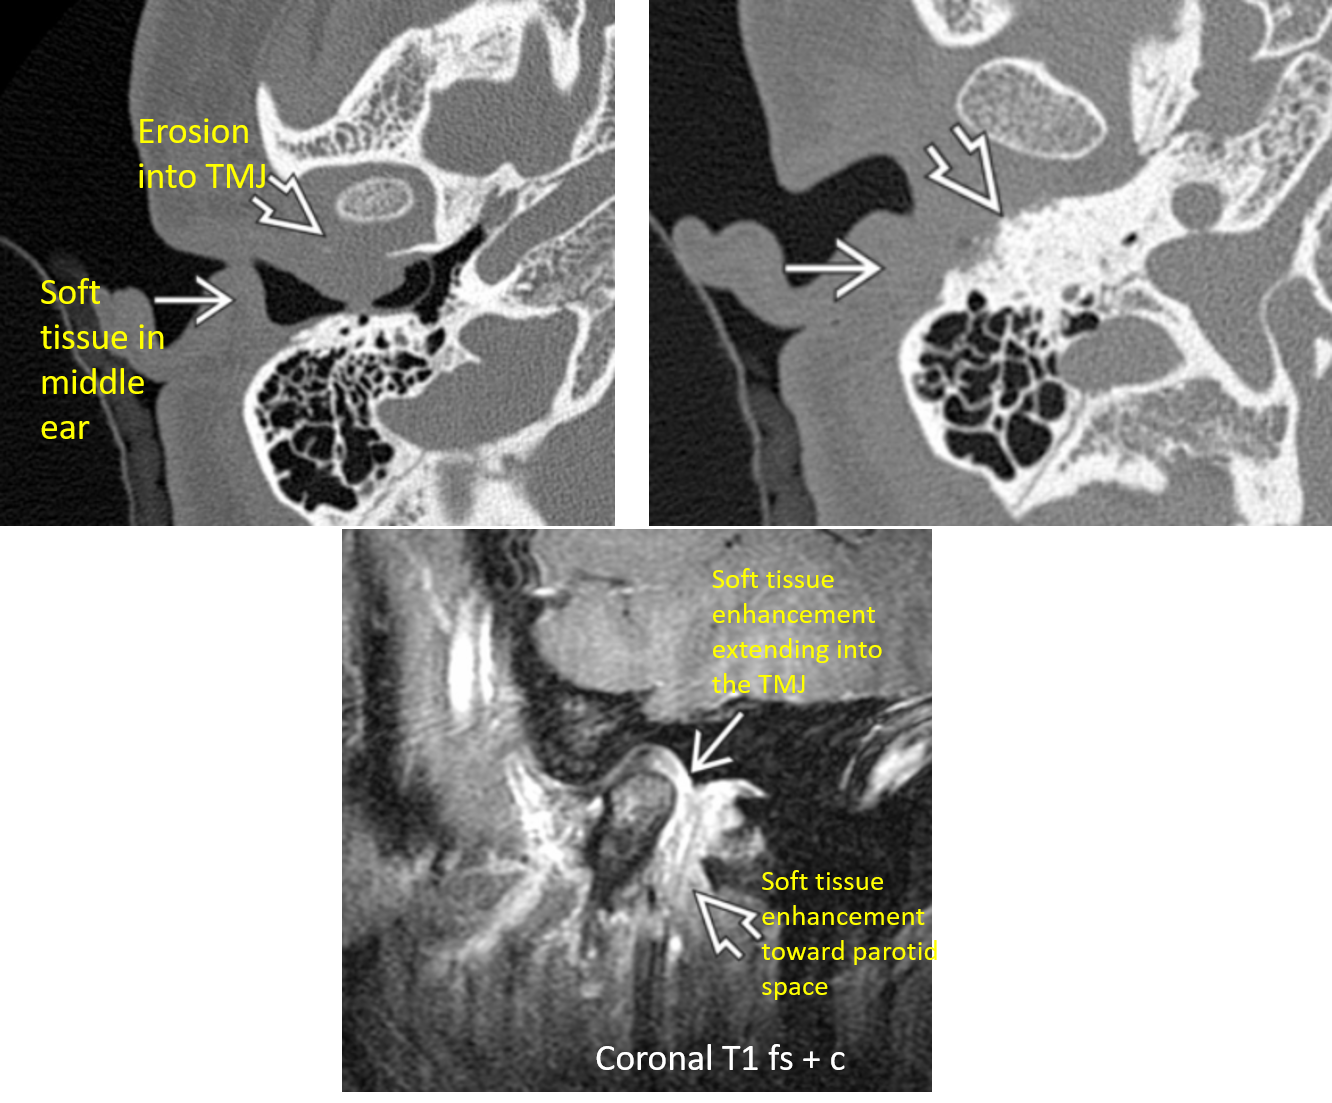

SCC of the EAC on CT and MR

axial bone algorithm CT shows soft tissue density in the EAC with osseous erosion. MR demostrates soft tissue enhancement.

Bone destruction and soft tissue invasion = aggressive malignancy